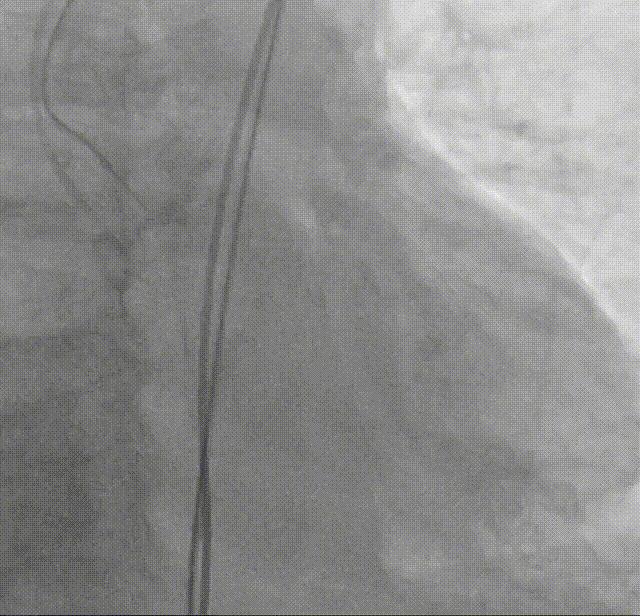

考虑瓣膜形态与位置均可,备球囊后扩处理方案,决定进行瓣膜脱钩,可见瓣膜脱钩稳定无位移

22mm球囊后扩:可见瓣膜形态明显改善

造影评估:瓣膜形态与位置理想,瓣周漏明显减少,导管测量跨瓣压差12mmHg

外周造影评估